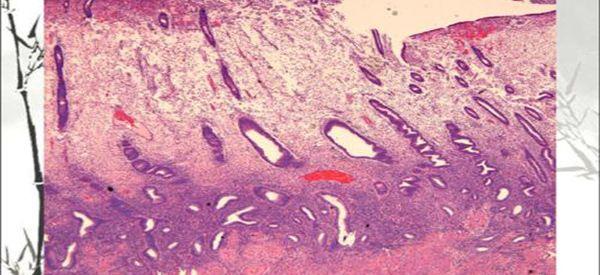

内膜活检可以排除子宫内膜疾病

1、子宫内膜诊刮术,操作过程中医生会先对患者的外阴皮肤进行消毒,然后用置阴道窥器,探测宫腔深度,再用小刮匙刮取内膜,将内膜组织装病理瓶内,固定并送病理学检查;

2、宫腔镜下子宫内膜诊刮术,故名思异就是在宫腔镜完成这项手术,操作过程中对医生的技术水平要求较高,在宫腔镜直视下刮取内膜组织送病理学检查。

虽然女性做内膜活检不打麻药是有一些疼,但内膜活检的目的主要是为了看女性子宫内是否有病变,如果有,则要明确病变的性质,并针对性进行调理后,才能提高试管胚胎移植率。